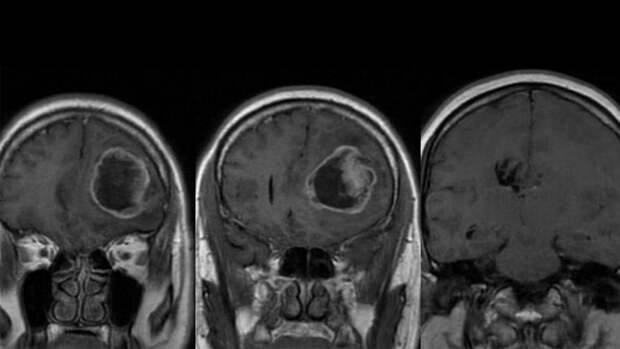

Диагноз журналисту поставили больше года назад. Розанов заявил, что у него искали инсульт, однако после обследования выяснилось, что у него онкология.